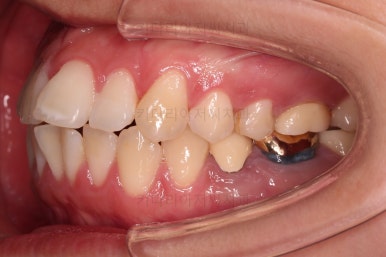

어느새 틈도 다 닫히고요.

마무리 과정만 남았습니다.

4. 마무리

틈이 다 없어졌고, 교합도 양호합니다.

무엇보다 임플란트 없이 결손부위가 깔끔하게 채워졌고요.

매우 다행으로 사랑니도 다 있었기 때문에 마치 큰 어금니가 다 있는 것과 같은 상황이 되었습니다.

역설적이게도 손상된 큰 어금니가 없었던 부위는 작은 어금니를 발치함으로 인해 오히려 치아 갯수가 모자라 보이는 상황까지 왔네요.(어금니가 결손된 부분이 더 자연스럽게 보이는 상황)